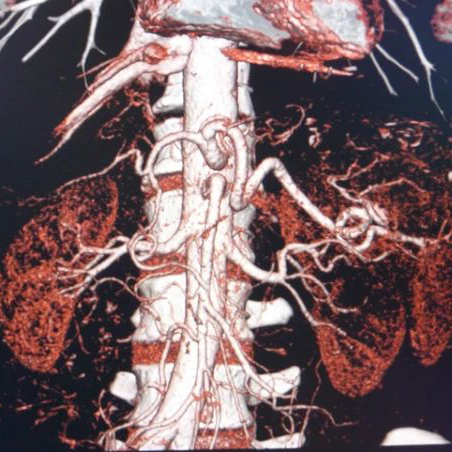

VASCULAR ANOMALIES OF THE KIDNEY

Renal hilar vessels

The renal hilum (Latin: hilum renale) or renal pedicle is the hilum of the kidney, that is, its recessed central fissure where its vessels, nerves and ureter pass. The medial border of the kidney is concave in the center and convex toward either extremity; it is directed forward and a little downward.

Renal artery - Right

Renal refers to anything related to the kidneys. Renal arteries carry blood from the heart to the kidneys. They branch directly from the aorta (the main artery coming off the heart) on either side and extend to each kidney. These arteries take a very large volume of blood to the kidneys to be filtered.

Renal artery - Left

Renal refers to anything related to the kidneys. Renal arteries carry blood from the heart to the kidneys. They branch directly from the aorta (the main artery coming off the heart) on either side and extend to each kidney. These arteries take a very large volume of blood to the kidneys to be filtered.